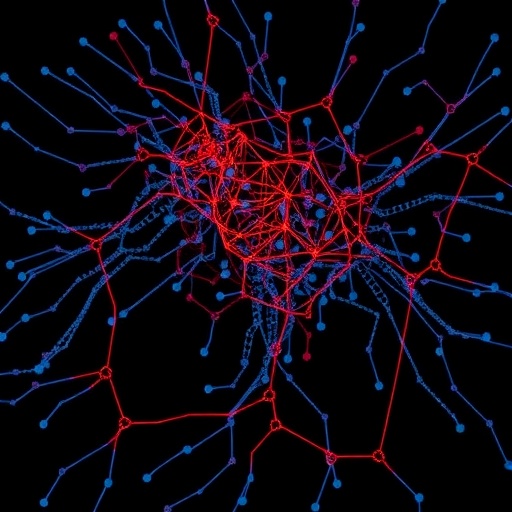

The study leverages cutting-edge single-cell RNA sequencing (scRNA-seq) technologies, which allow researchers to dissect complex tissues into their individual cellular components and capture their gene expression patterns with unprecedented resolution. This granular approach contrasts markedly from traditional bulk sequencing techniques, which average gene expression across heterogeneous cell populations, potentially masking subtle yet crucial cellular heterogeneity. By peeling back the layers of the BPH prostate, the investigators reveal distinct cellular states and transcriptional signatures that were previously obscured.

Through careful isolation and analysis of thousands of single cells derived from hyperplastic prostate tissue, the research team delineated the cellular ecosystem driving the pathological enlargement. Their data uncovered a diverse assembly of epithelial, stromal, and immune cells, each exhibiting specific gene expression profiles that hint at unique functional roles in disease pathogenesis. Notably, the study identified subsets of basal and luminal epithelial cells exhibiting aberrant proliferative and secretory signatures, shedding light on how these populations may contribute to glandular overgrowth.

Moreover, the bioinformatic methodologies employed—incorporating dimensionality reduction, clustering algorithms, and pathway enrichment analyses—illustrate how computational biology synergizes with experimental data to transform vast sequencing reads into biologically interpretable insights. This underscores the increasing indispensability of integrative approaches in contemporary biomedical research.